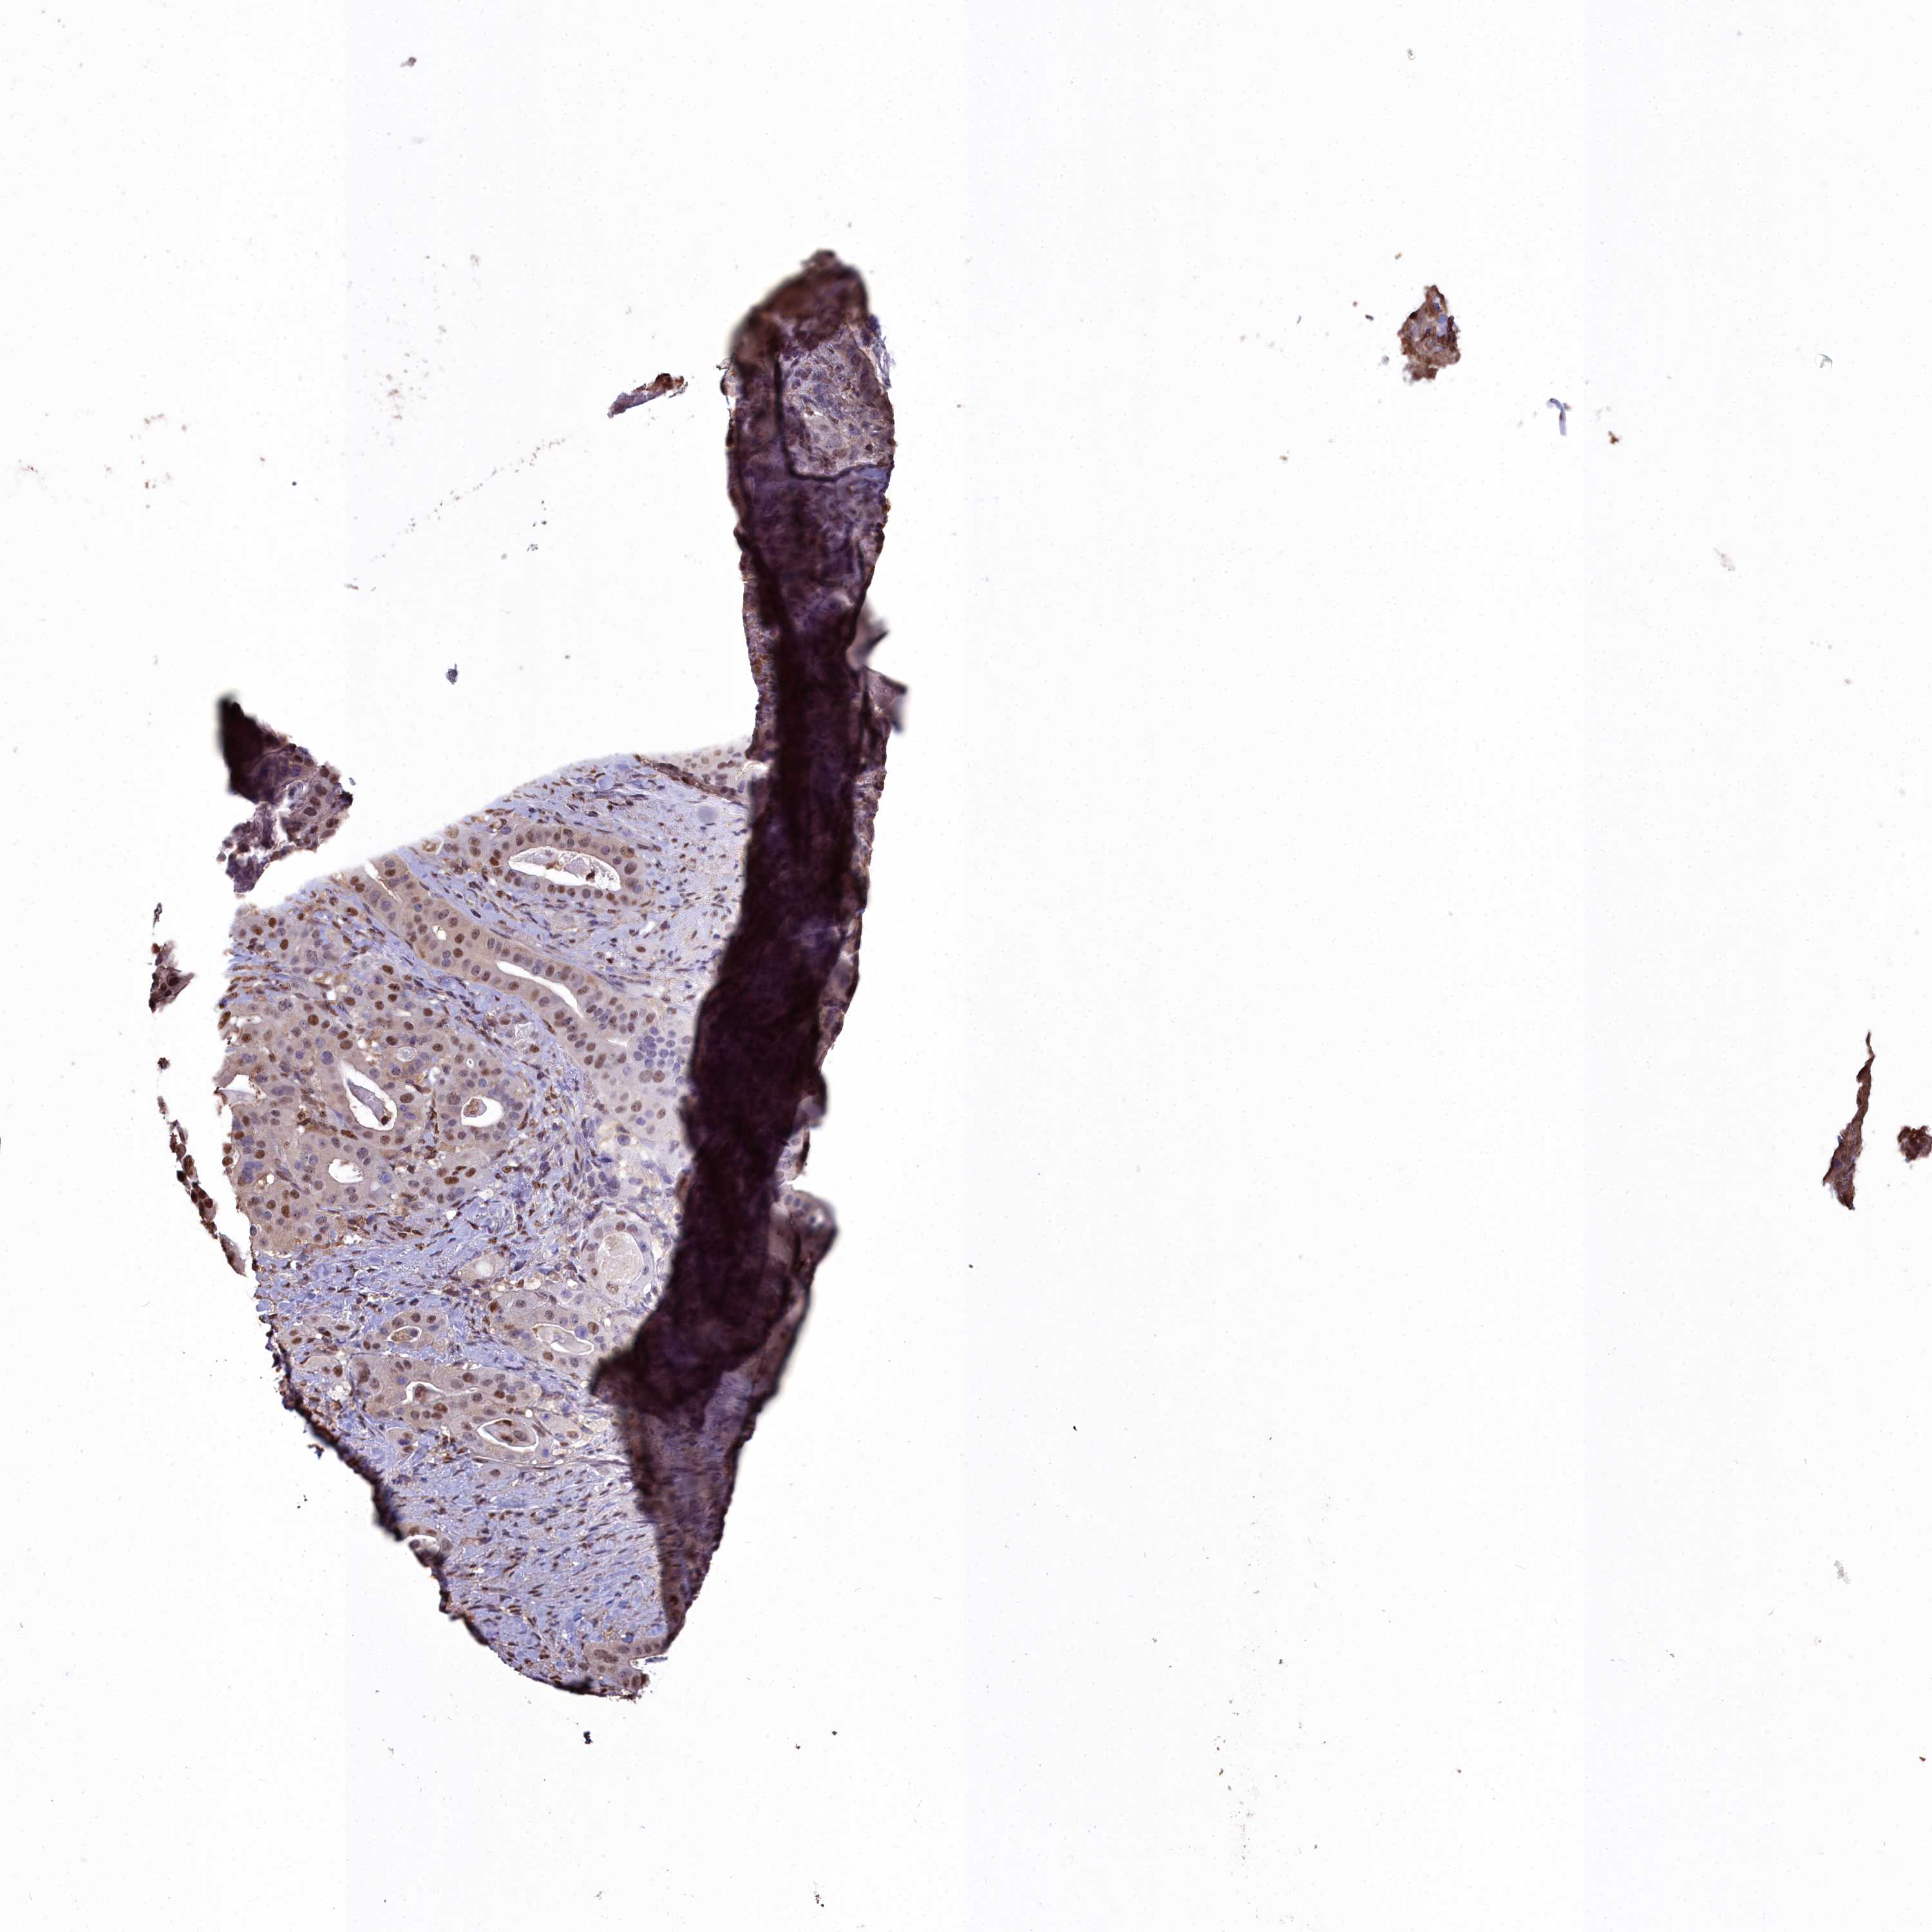

STOMACH CANCER - Protein expressioni

A mouse-over function shows sample information and annotation data. Click on an image to view it in a full screen mode. Samples can be filtered based on level of antibody staining by selecting one or several of the following categories: high, medium, low and not detected. The assay and annotation is described here.

Note that samples used for immunohistochemistry by the Human Protein Atlas do not correspond to samples in the TCGA dataset.

Antibody stainingi

Antibody staining in the annotated cell types in the current human tissue is reported as not detected, low, medium, or high, based on conventional immunohistochemistry profiling in selected tissues. This score is based on the combination of the staining intensity and fraction of stained cells.

Each image is clickable and will lead to virtual microscopy that enables deeper exploration of all samples and also displays staining intensity scores, fraction scores and subcellular localization as well as patient and tissue information for each sample.

HPA040067

HPA061280

CAB005197

CAB016392

CAB079968

Adenocarcinoma, NOS

Adenocarcinoma, High grade